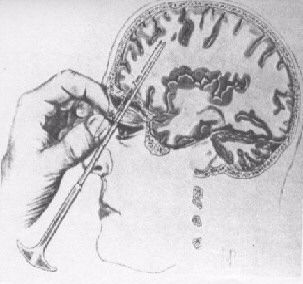

ロボトミー

1935年、ジョン・フルトン(John

Fulton)とカーライル・ヤコブセン(Carlyle

Jacobsen)がチンパンジーにおいて前頭葉切断を行ったところ、性格が穏やかになったと報告したのを受け、同年、ポルトガルの神経科医エガス・モニスがリスボンのサンタマルタ病院で外科医のペドロ・アルメイダ・リマ(Pedro

Almeida

Lima)と組んで、初めてヒトにおいて前頭葉切裁術(前頭葉を脳のその他の部分から切り離す手術)を行った。その後、1936年9月14日ワシントンDCのジョージ・ワシントン大学でも、ウォルター・フリーマン

(Walter Jackson Freeman II)

博士の手によって、米国で初めてのロボトミー手術が激越性うつ病患者(63歳の女性)におこなわれた。当時に於いて治療が不可能と思われた精神的疾病が外科的手術である程度は抑制できるという結果は注目に値するものであって世界各地で追試され、成功例も含まれたものの、特にうつ病の患者の6%は手術から生還することはなかった。また生還したとしても、しばしばてんかん発作、人格変化、無気力、抑制の欠如、衝動性などの重大かつ不可逆的な副作用が起こっていた。